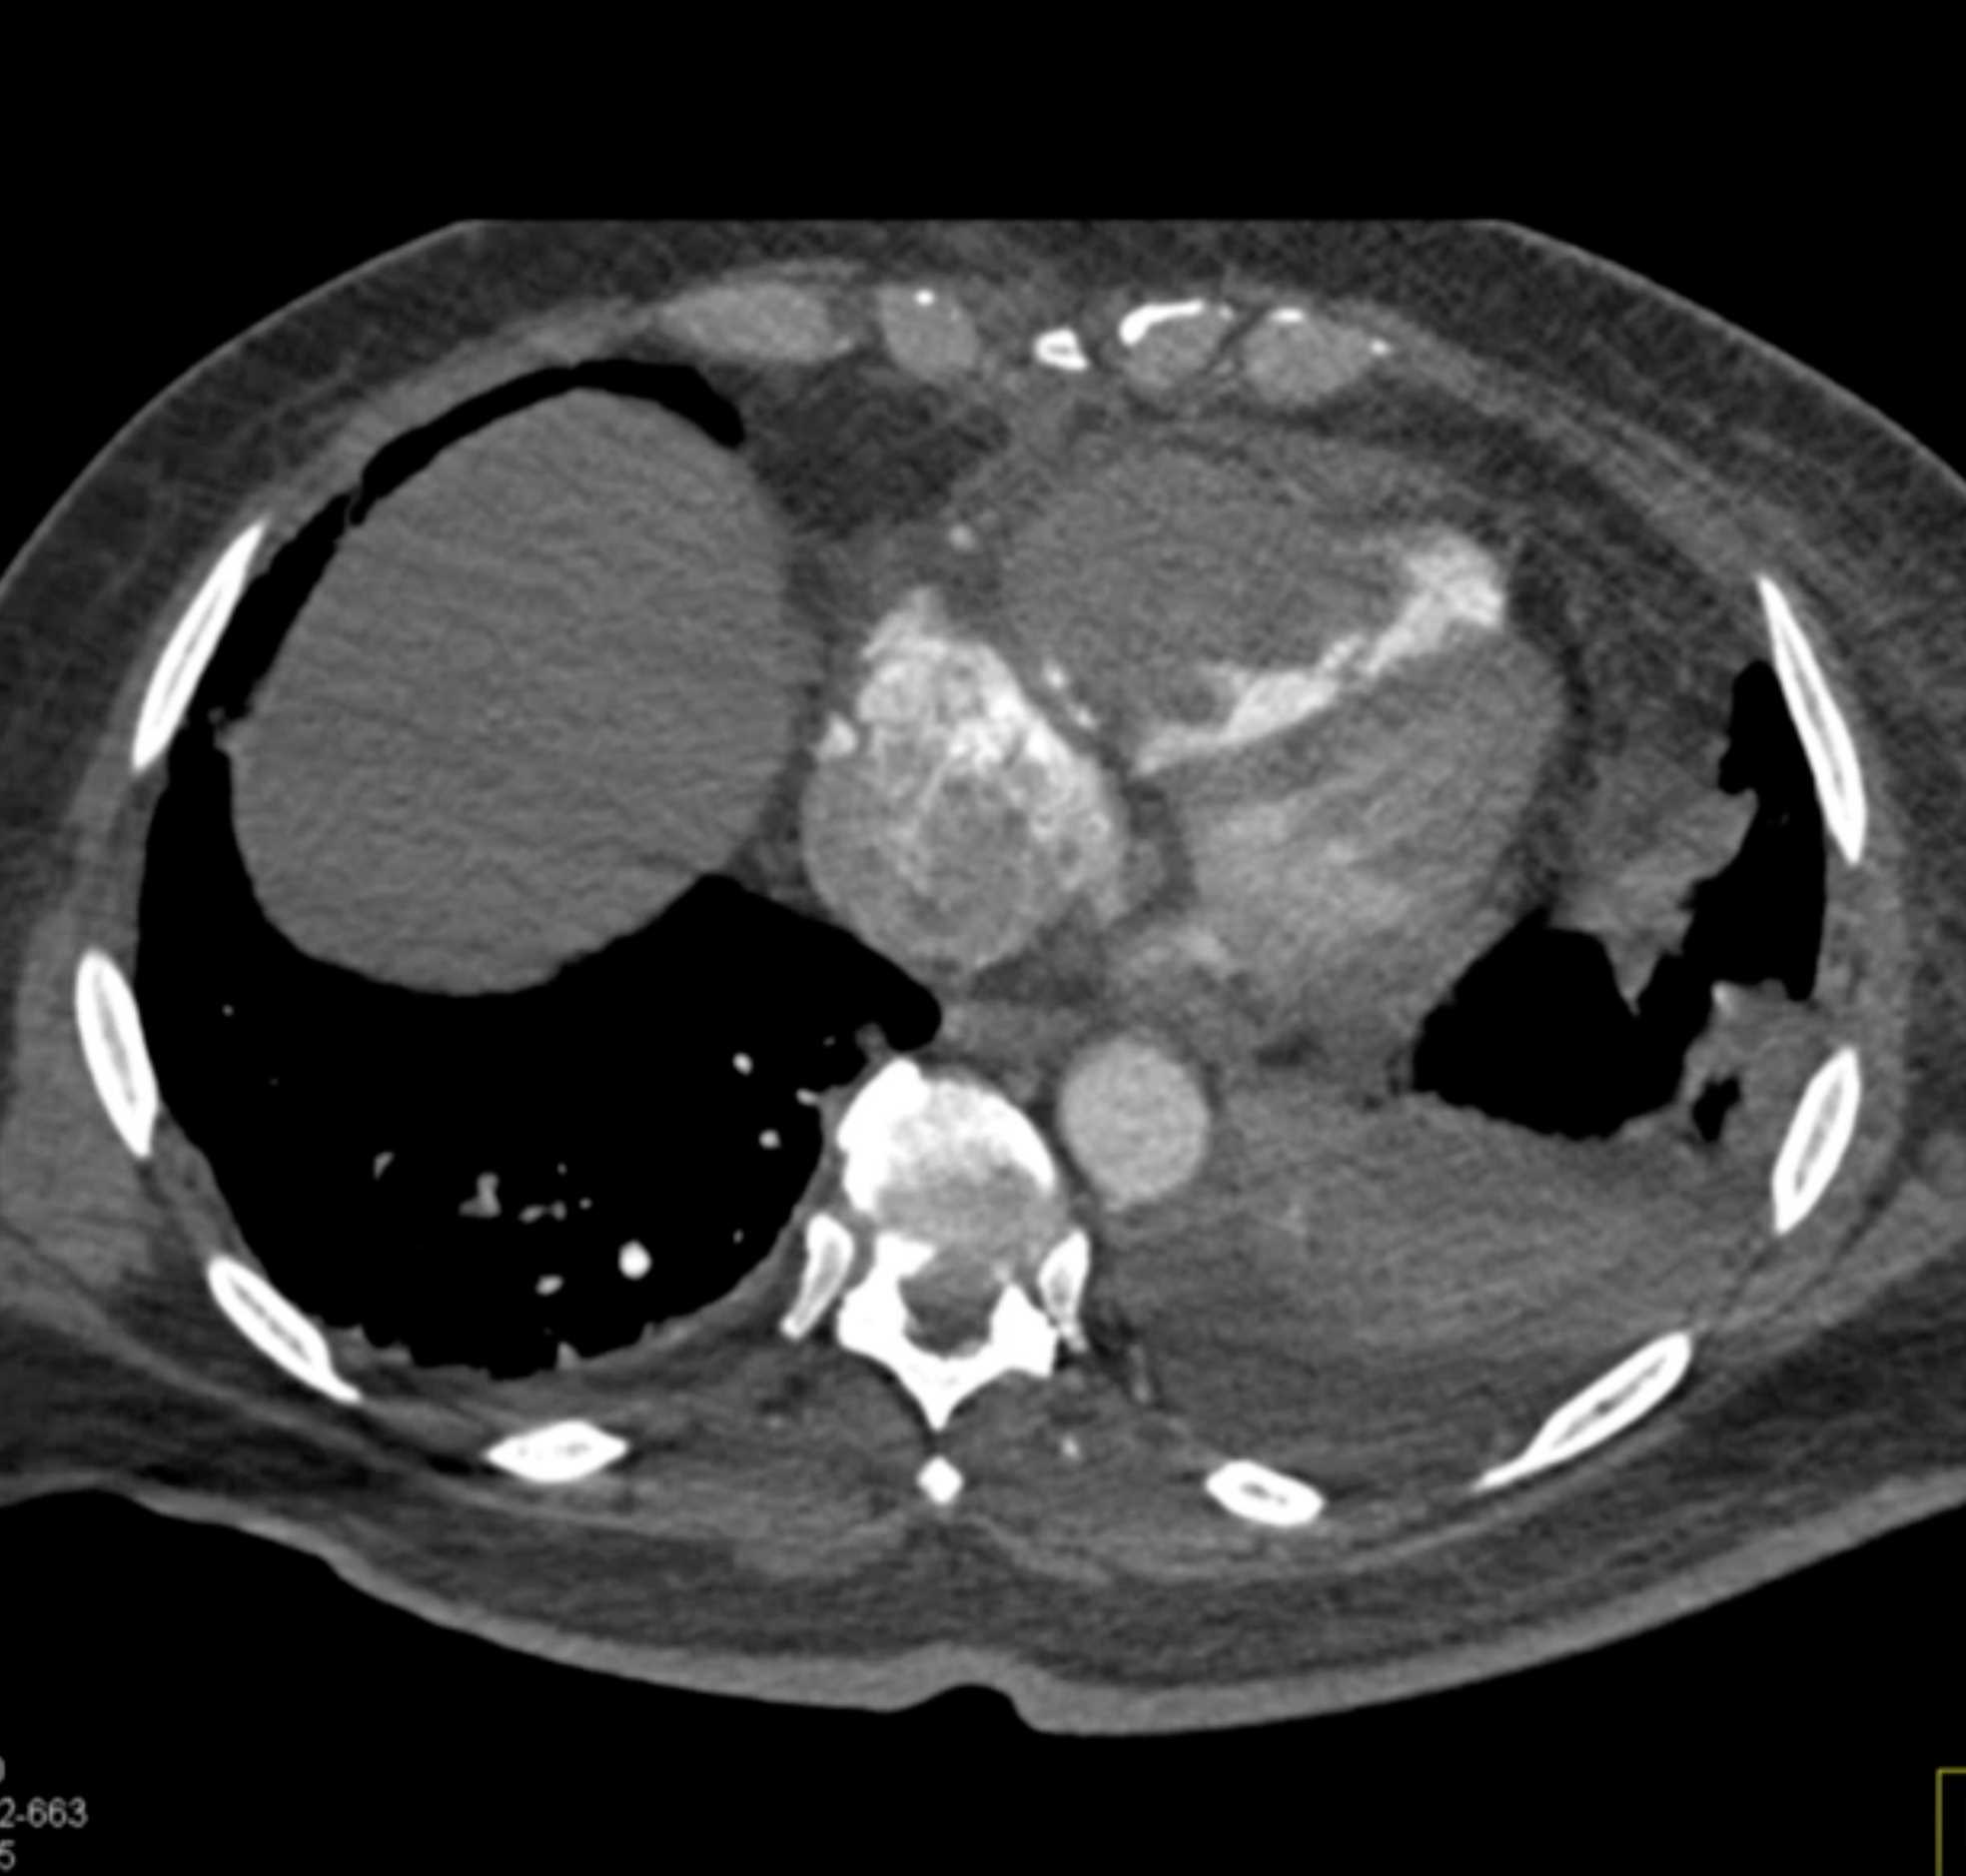

Primary Spindle Cell Carcinoma of the Right Ventricle